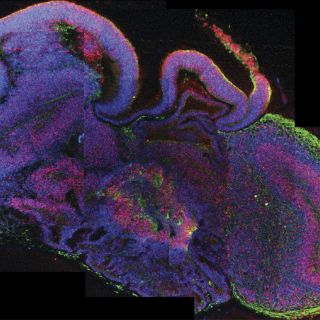

Los microcerebros están formados por diferentes tejidos dispuestos en capas

Estos microcerebros, que incluyen la corteza cerebral que cubre los dos hemisferios, están formados por diferentes tejidos dispuestos en capas, cuya organización guarda muchas semejanzas con la de un cerebro en sus etapas más tempranas de desarrollo.